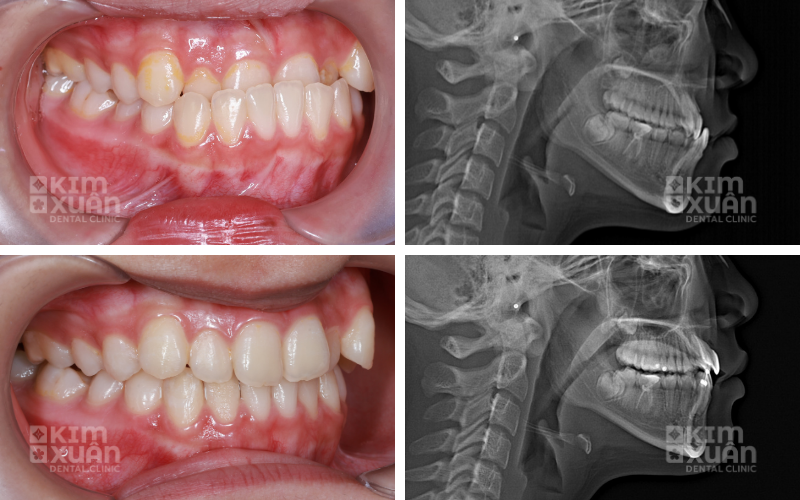

6. Vì Sao Nên Niềng Răng Tại Nha Khoa Kim Xuân?

Lựa chọn địa chỉ niềng răng uy tín đóng vai trò quan trọng trong việc quyết định hiệu quả và độ ổn định lâu dài sau chỉnh nha. Tại Nha khoa Kim Xuân, khách hàng niềng răng được đảm bảo:

-

Phác đồ chỉnh nha cá nhân hóa cho từng khách hàng, phù hợp tình trạng răng - khớp cắn

Trang thiết bị hiện đại, chụp phim và phân tích khớp cắn kỹ lưỡng trước khi điều trị

Bảng giá niềng răng rõ ràng, minh bạch ngay từ đầu, không phát sinh ngoài kế hoạch

Theo dõi sát sao trong suốt quá trình niềng răng, điều chỉnh kịp thời khi cần thiết

Hỗ trợ tư vấn tận tâm trước - trong - sau niềng, giúp khách hàng an tâm xuyên suốt quá trình điều trị